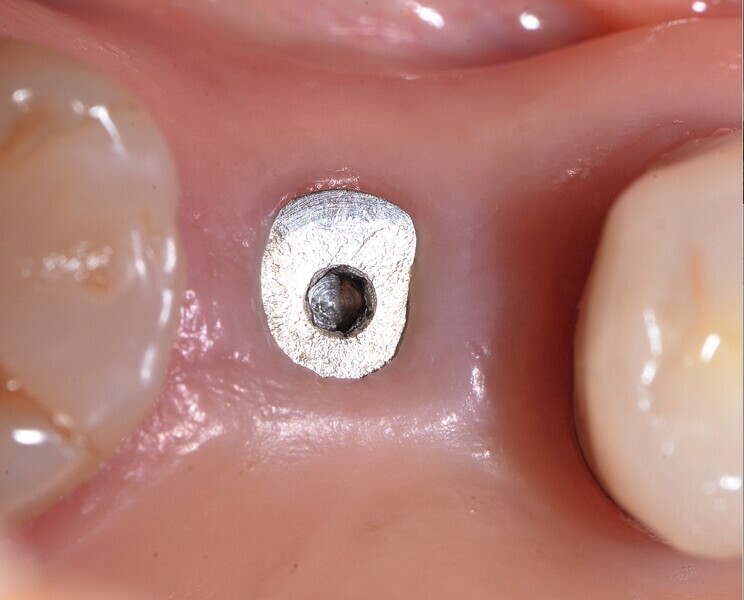

Fig. 38 : Pose de l’implant deux pièces en céramique au niveau tissulaire.

Fig. 39 : Pose de l’implant deux pièces en céramique au niveau tissulaire.

Fig. 40 : Pose de l’implant deux pièces en céramique au niveau tissulaire.

Un patient présentant un défaut infraosseux s’est présenté au cabinet dentaire avec le souhait explicite d’un traitement par un implant en zircone, pour remplacer l’une de ses molaires. Un implant deux pièces en zircone a donc été posé et le défaut infra-osseux a été traité dans le même temps, au moyen d’une allogreffe osseuse et du dérivé de matrice amélaire Emdogain (Straumann). La mise en charge n’a pas été réalisée à ce stade (Figs. 35–45).